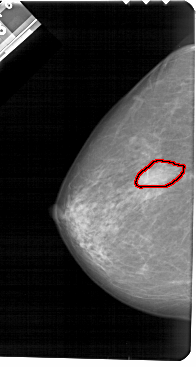

A_1483_1.LEFT_MLO

FILE: A_1483_1.LEFT_MLO.OVERLAY

TOTAL_ABNORMALITIES 1

ABNORMALITY 1

LESION_TYPE MASS SHAPE IRREGULAR MARGINS ILL_DEFINED

ASSESSMENT 4

SUBTLETY 5

PATHOLOGY BENIGN

TOTAL_OUTLINES 1

BOUNDARY